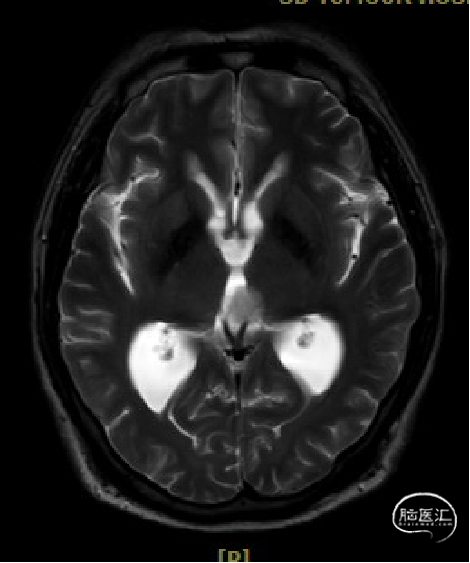

患者5年前无明显诱因出现阵发性头晕,无明显头痛、恶心呕吐等不适,开始未予重视,2022-7-19出现头晕加重,伴视力下降,遂于2022-7-24在当地医院行颅脑MRI提示:松果体区肿瘤伴梗阻性脑积水。

于该院在2022-7-27全麻下行松果体区病灶部分切除活检+神经内镜下第三脑室底造瘘术,术后由于取出肿瘤组织少,未能明确病理结果。患者术后恢复顺利,为进一步治疗就诊于我院。

入院检查

松果体区占位,胶质瘤?生殖细胞肿瘤?

脑积水

脑梗死